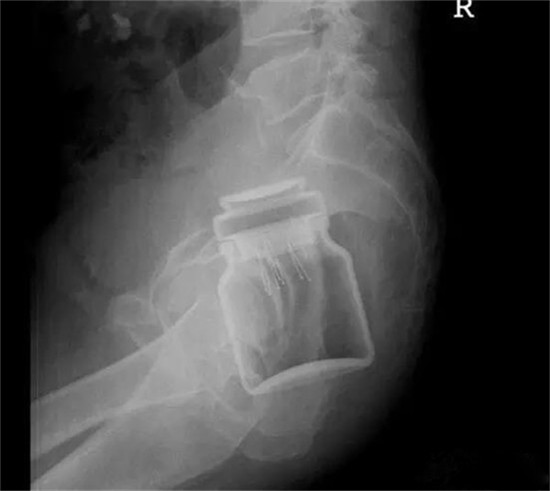

这个是什么瓶子?

这也是一个玻璃瓶。也需要麻醉下取出来。

杯子。

这个还是比较常见的,认得出来吗?

男性病人,也是个杯子。

这个也是一个玻璃杯。